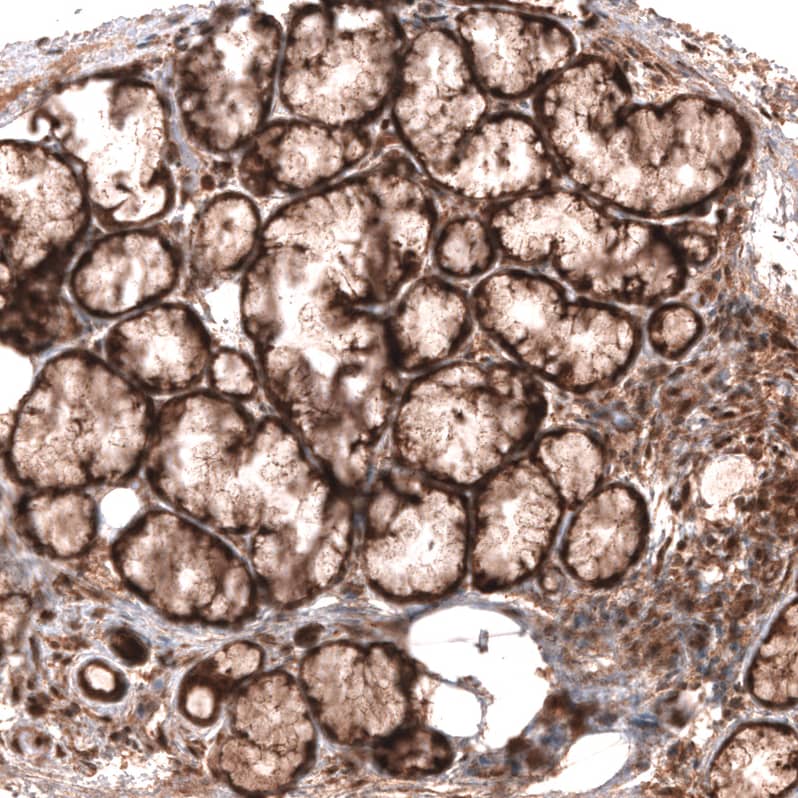

Staining of human salivary gland shows moderate cytoplasmic positivity in glandular cells.